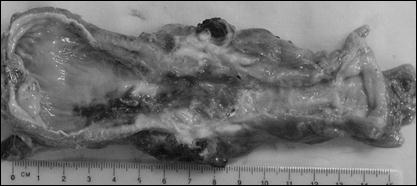

Рис. 3. Препарат резецированного пищевода. Длинная стриктура верхне- и среднегрудного отд. пищевода и вторичная кольцевидная стриктура дистального отд. пищевода.